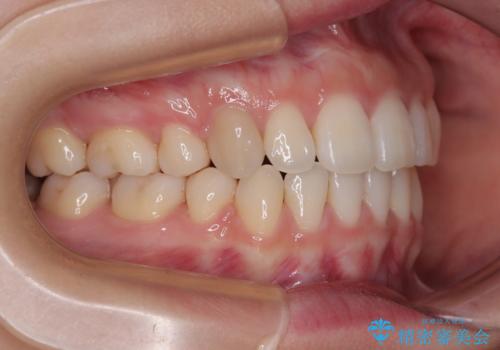

横顔の印象を変えたい ワイヤー装置での抜歯矯正

- 口元の突出感と上下前歯のズレを気にして来院された患者様です。

舌の突出癖により上下の前歯は非接触となっている状態でした。

舌のトレーニングを行わないと上下前歯の接触達成は困難であるため、トレーニングをしっかりと行っていただきながら、治療を進めて行くこととしました。

突出感改善のため、上下左右の第一小臼歯4本を抜歯し、ワイヤー装置にて矯正治療を行うこととしました。

舌のトレーニングをしっかりと行ってくださり、予定通りの期間で理想的な仕上がりを達成することができました。